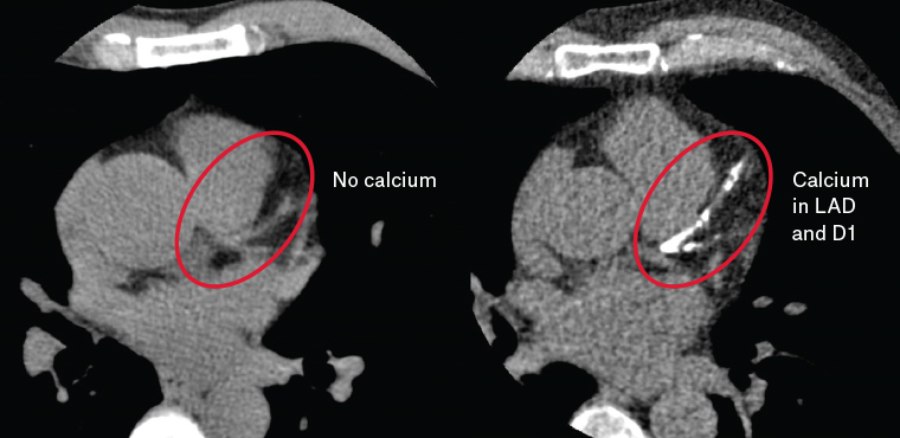

أكد استشاري أمراض القلب وقسطرة الشرايين، د. خالد النمر، أن وجود التكلّس في الشرايين التاجية لا يُعدّ دليلاً مباشراً على وجود تضيق مُعيق لتدفق الدم أو نقص في التروية القلبية.

وأوضح النمر أن التكلّس بحد ذاته لا يستدعي بالضرورة تركيب دعامة، مشيراً إلى أن قرار التدخل العلاجي يعتمد على التقييم السريري المتكامل، ووجود الأعراض، وإثبات نقص التروية بوسائل التشخيص المناسبة.